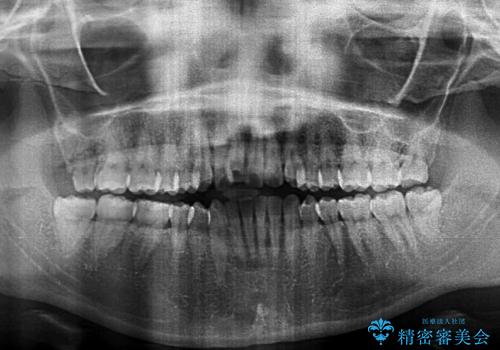

- 上下のデコボコを改善したいとのことで来院された患者様です。

近々妊娠する予定であり、極力短期間で治療したいとのことで、ワイヤー装置による非抜歯矯正治療を行うこととしました。